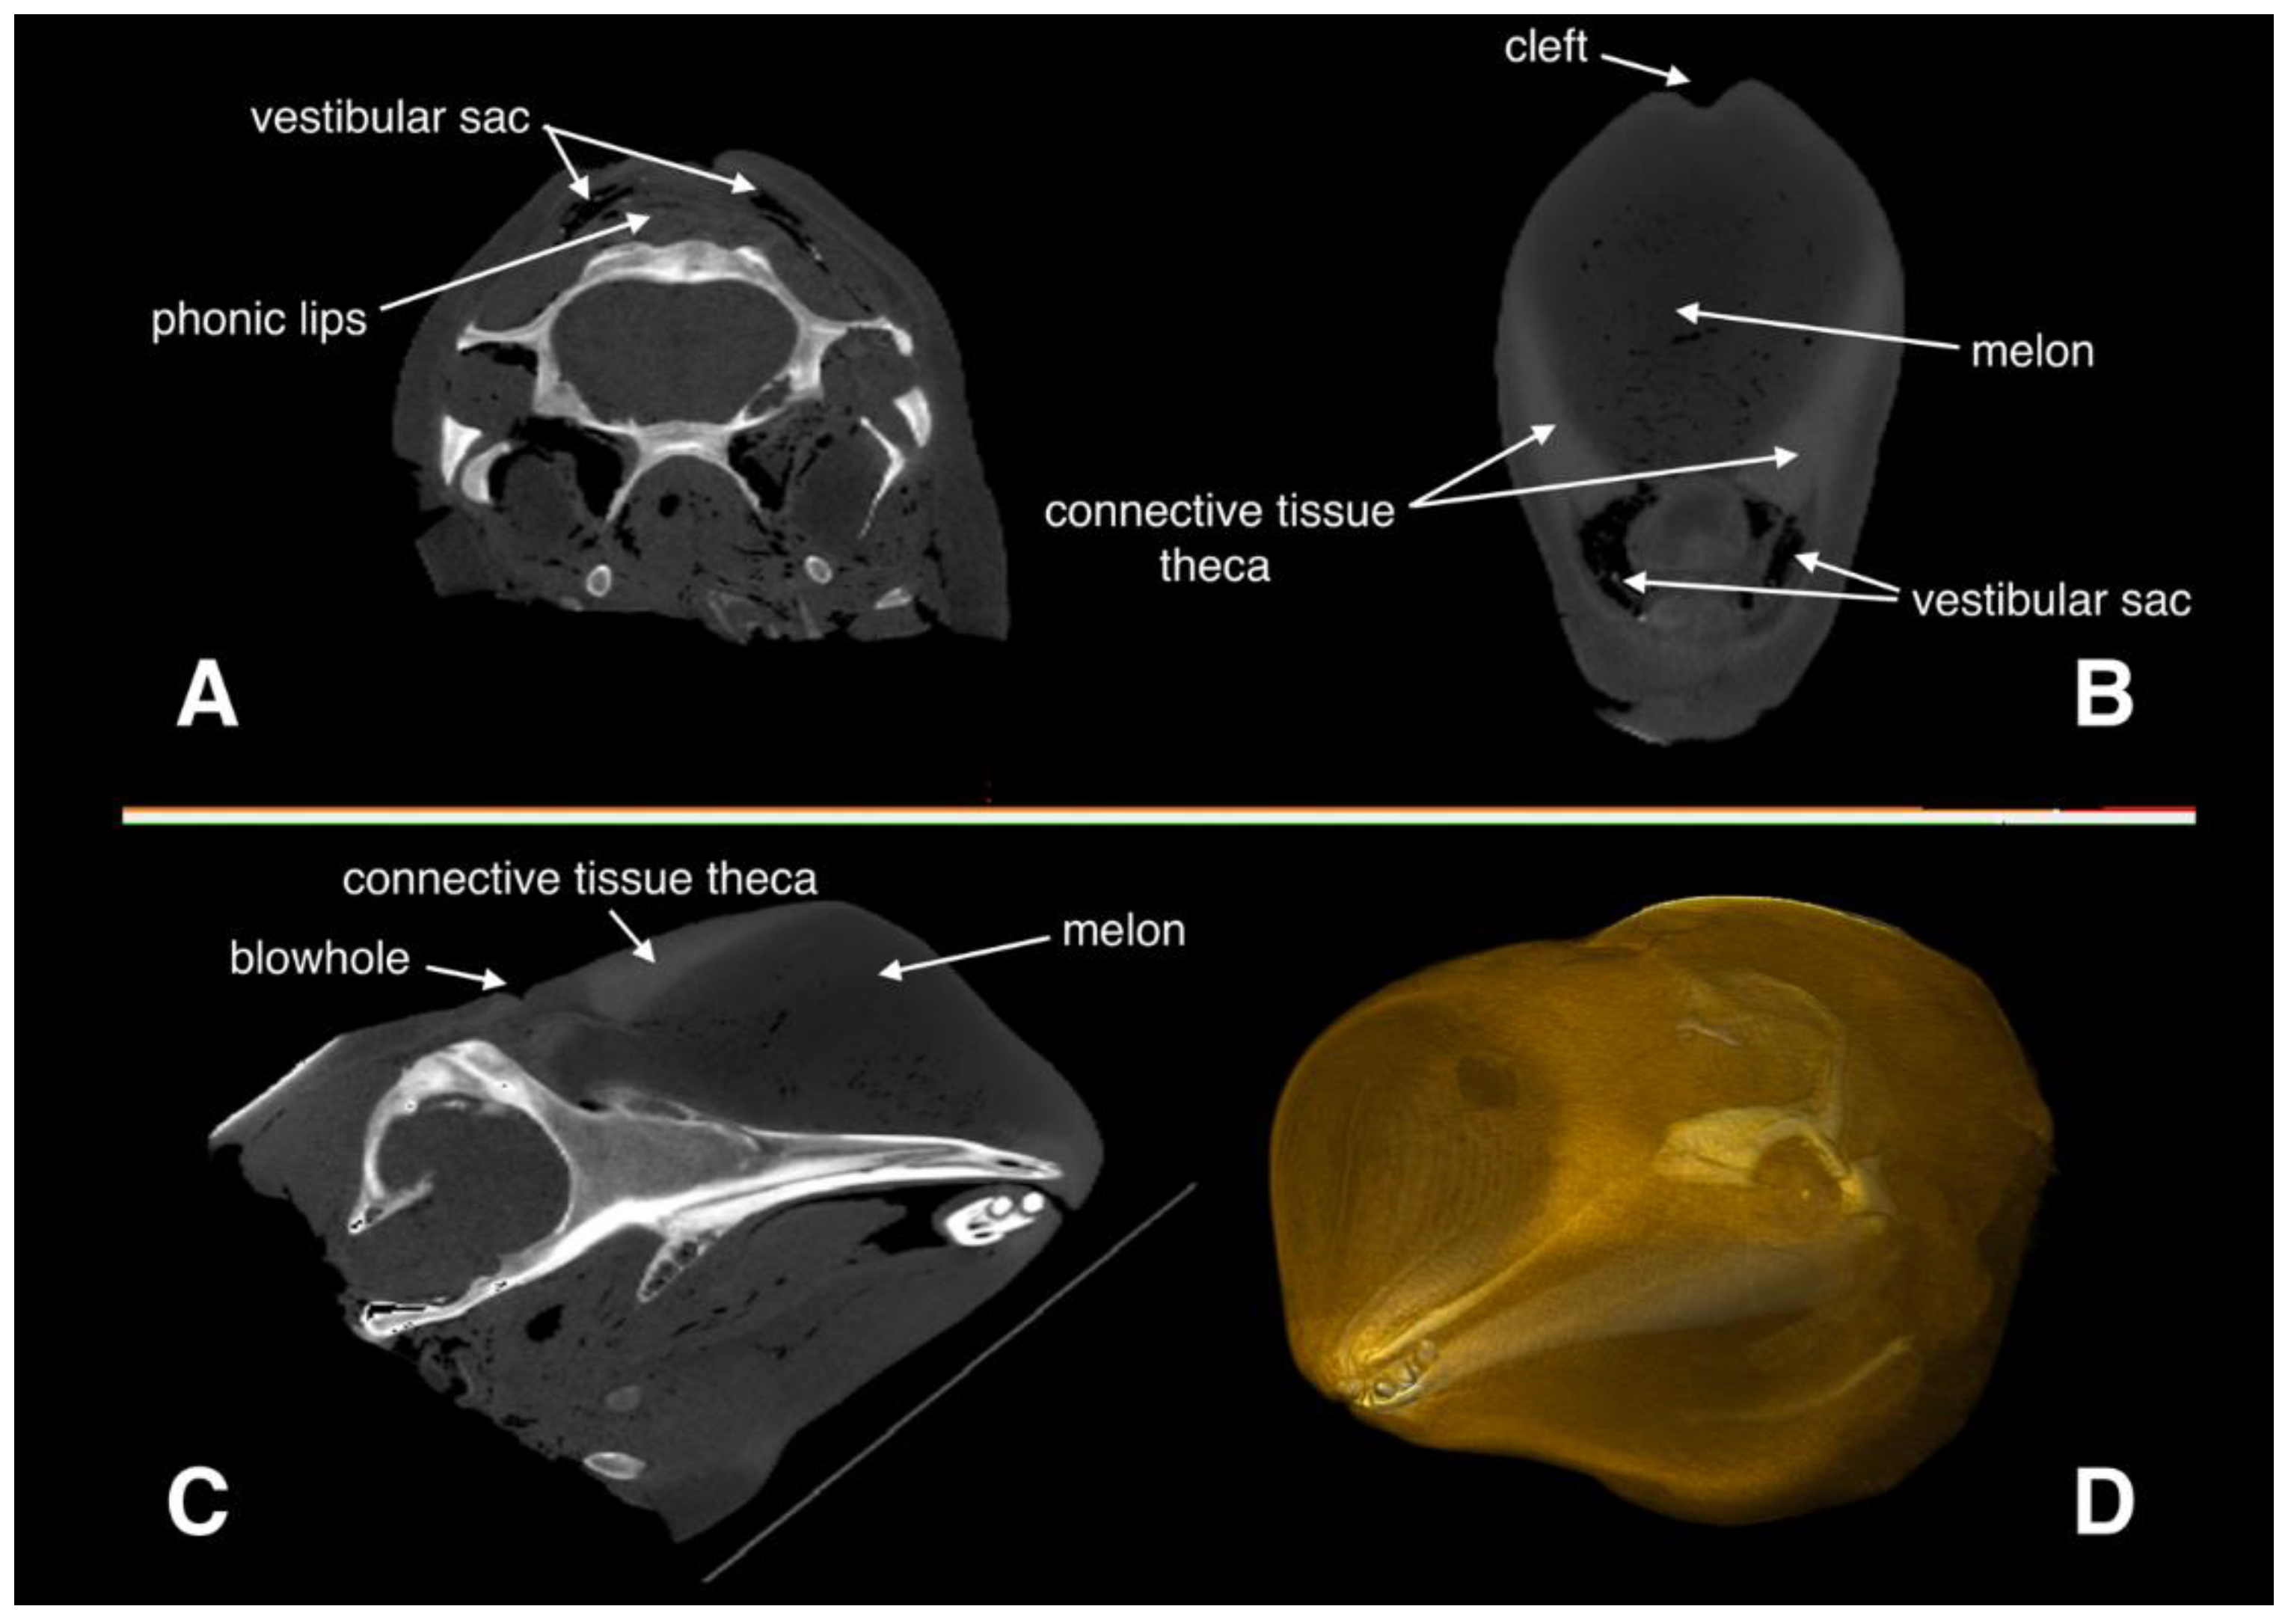

2.1. Medical CT Scan and Image Analysis